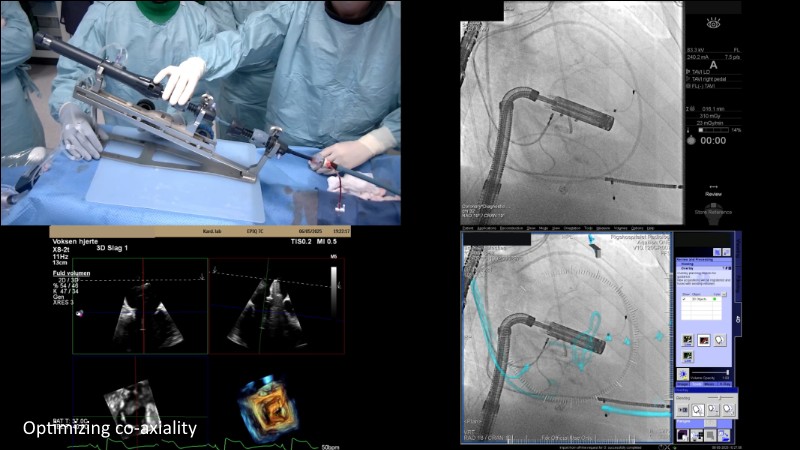

This EuroPCR 2025 session highlights the evolving role of transcatheter mitral valve replacement, focusing on the clinical potential of mitral regurgitation elimination. Get an overview of the current status of the Intrepid TMVR programme, learn about the transition to the 29Fr transfemoral system, and explore how patient screening—especially in the presence of mitral annular calcification—impacts procedural planning. Real-world case reviews from the APOLLO-EU trial offer practical insights into how this next-generation system is being applied in Europe today.